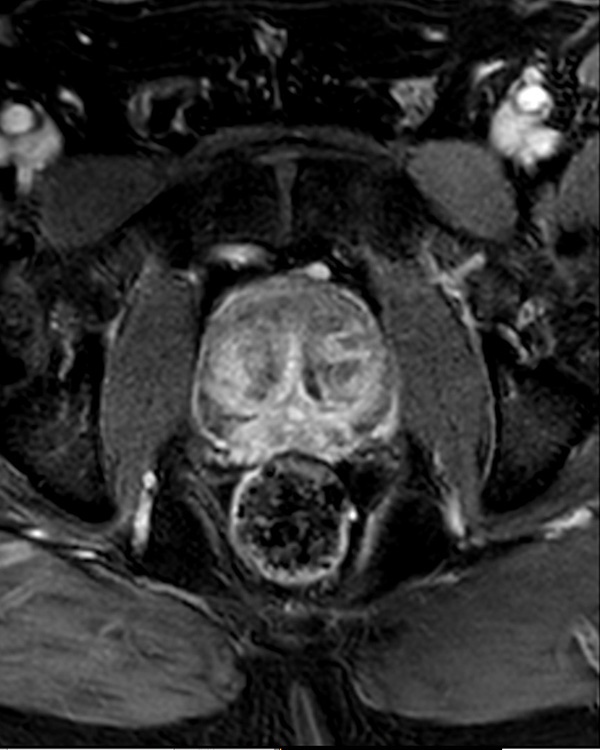

A 60-year-old male with elevated PSA and weak urinary stream underwent MRI. The exam includes high resolution DWI and ADC mapping as well as dynamic imaging. The prostate gland measures 5.2 x 4.4 x 5.9 cm in maximal transverse, AP, and craniocaudal dimensions, respectively, corresponding to an approximate glandular volume of 70 ml. Heterogeneous nodular hypertrophy is seen along the central transitional zone, with hypointense pseudo capsule, indicative of BPH, without dominant T2-hypointense nodules. Patchy T2-hypointense foci are noted throughout the peripheral zone bilaterally at the base, mid-gland and apex, with total PI-RADS score 6, so probably benign. No dominant nodular areas of restricted diffusion are evident. A geographic T2-hyperintense focus in the peripheral zone at the right base to mid-gland, paramidline shows asymmetric restricted diffusion, total PI-RADS score 10. No dominant lesions, greater than 1 cm. Clinical correlation and follow-up are advised.